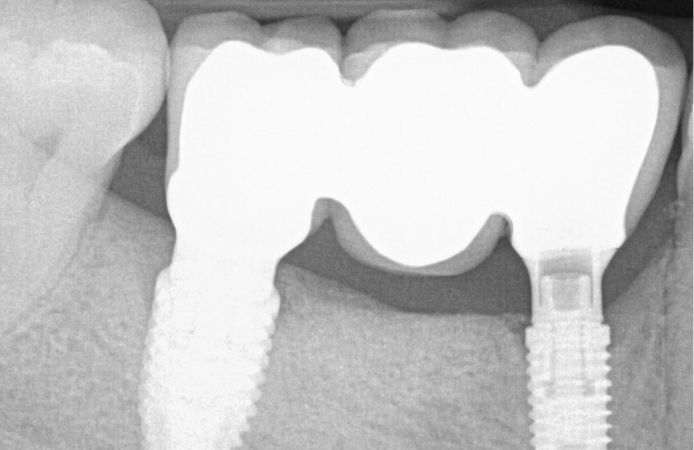

Figure 13.

Radiograph six months after implant placement with final restoration. The bone level is stable at implant level.